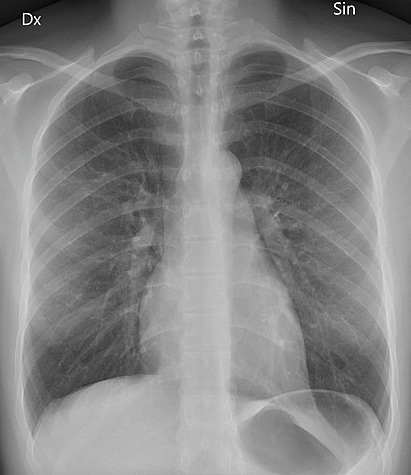

Posteroanterior chest X-ray

Mikael Häggström, CC0, via Wikimedia Commons